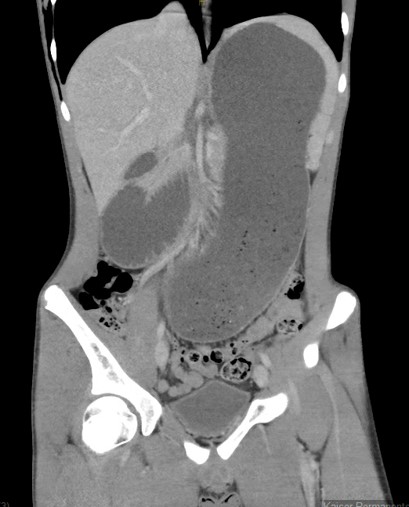

Computed tomography downloaded from Occupational Safety and Health

CT Scan

YouTube link for the initial CT scan is available at https://youtu.be/jG0J2b3EhhU.

Impression

Extensive air surrounded the esophagus and within the mediastinum, with dissecting along soft tissue planes, as described, suggestive of an esophageal perforation.

There is no free air in the abdomen. There is dilated stomach and proximal duodenum, with narrowing of the duodenum as it crosses the superior mesenteric artery (SMA). This can be seen with SMA syndrome in the proper clinical setting.